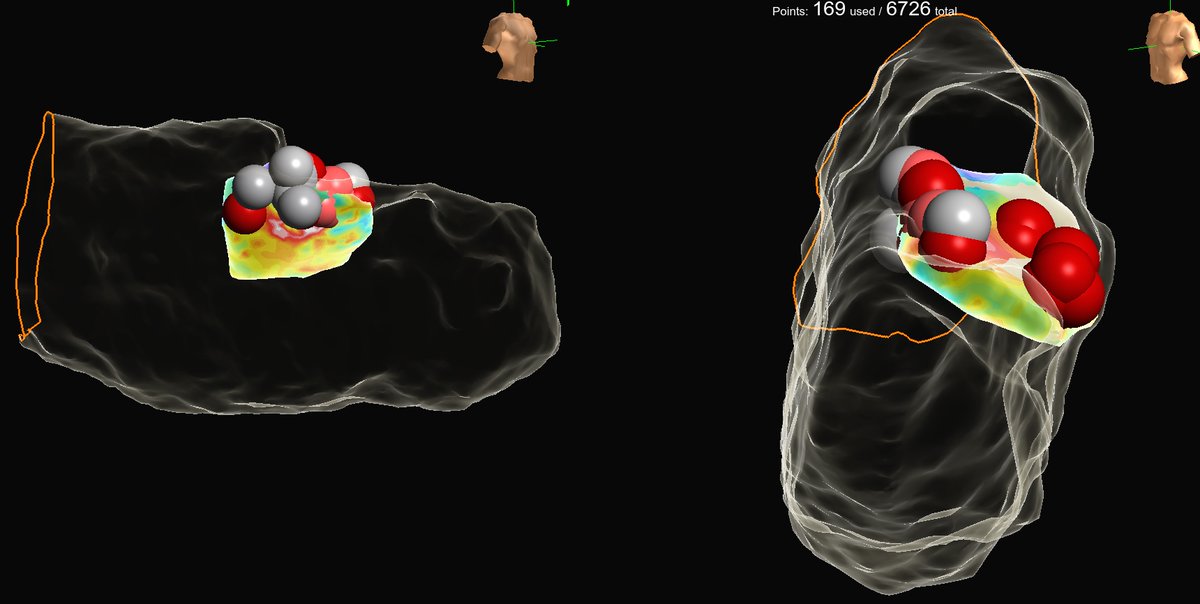

Volt released some pretty impressive 12 month data with over 80% success in paroxysmals and excellent persistent AF results. Read the simultaneous publication! kwnsfk27.r.eu-west-1.awstrack.me/L0/https:%2F%2…